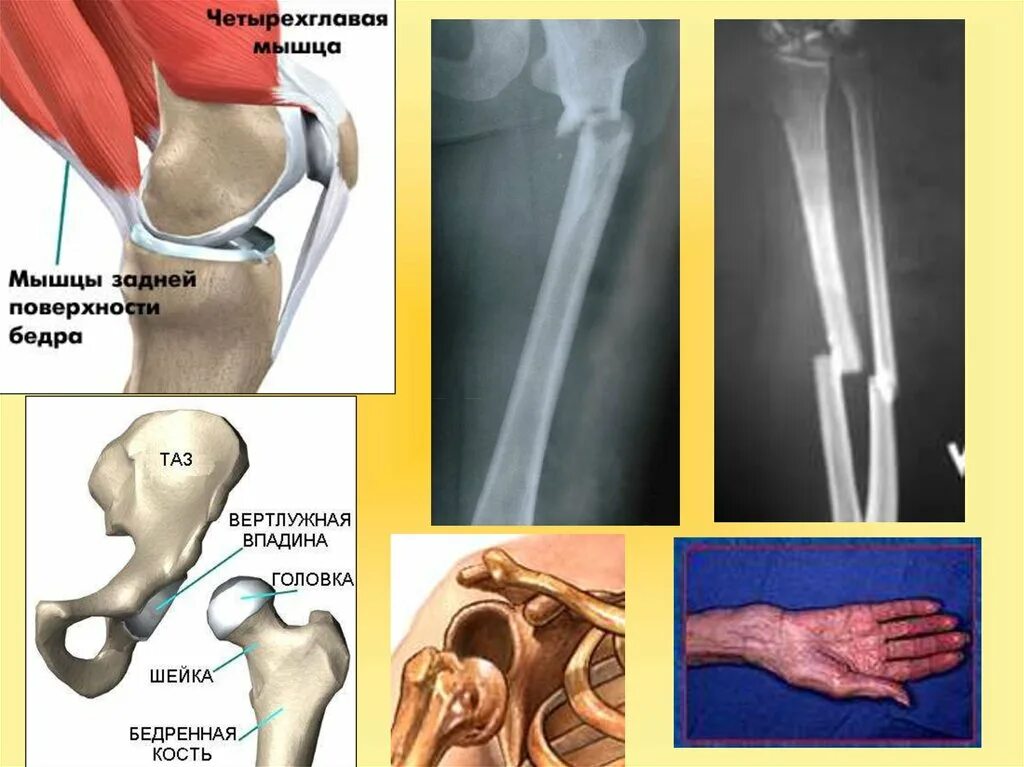

Переломы вывихи растяжения связок ушибы